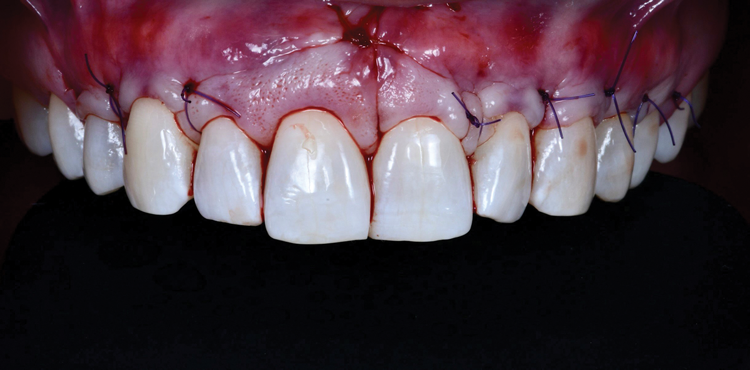

(9.) Immediate postoperative view after final closure.

Figure 9

Mobility of the anterior tunnel portion of the flap was achieved by scoring the periosteum through the frenectomy incision. The flap release in the posterior envelope sections of the flap was achieved through the coronal (ie, sulcular) area. These steps were important to both create space for the graft material and ensure complete passive closure over the graft without excess flap tension. After this, the NCCLs were smoothed with rotary instruments to provide smooth, flat (or concave) surfaces. A soft-tissue allograft was then introduced through the frenectomy incision, passed through the "channel" over the incisors, and then retrieved through the envelope portion of the flap on both the left and right sides. After the graft was sutured to the CEJs with independent sling sutures using 4-0 chromic gut sutures (as can be seen in Figure 4), the overlying flap was coronally advanced over the allograft and sutured with independent sling sutures using 4-0 polypropylene sutures, and the frenum was closed with interrupted sutures also using 4-0 polypropylene sutures (Figure 9). To confirm passive closure of the flap, the patient's lips and cheeks were then manipulated in various directions. Care was taken to be sure that no allograft material was exposed.